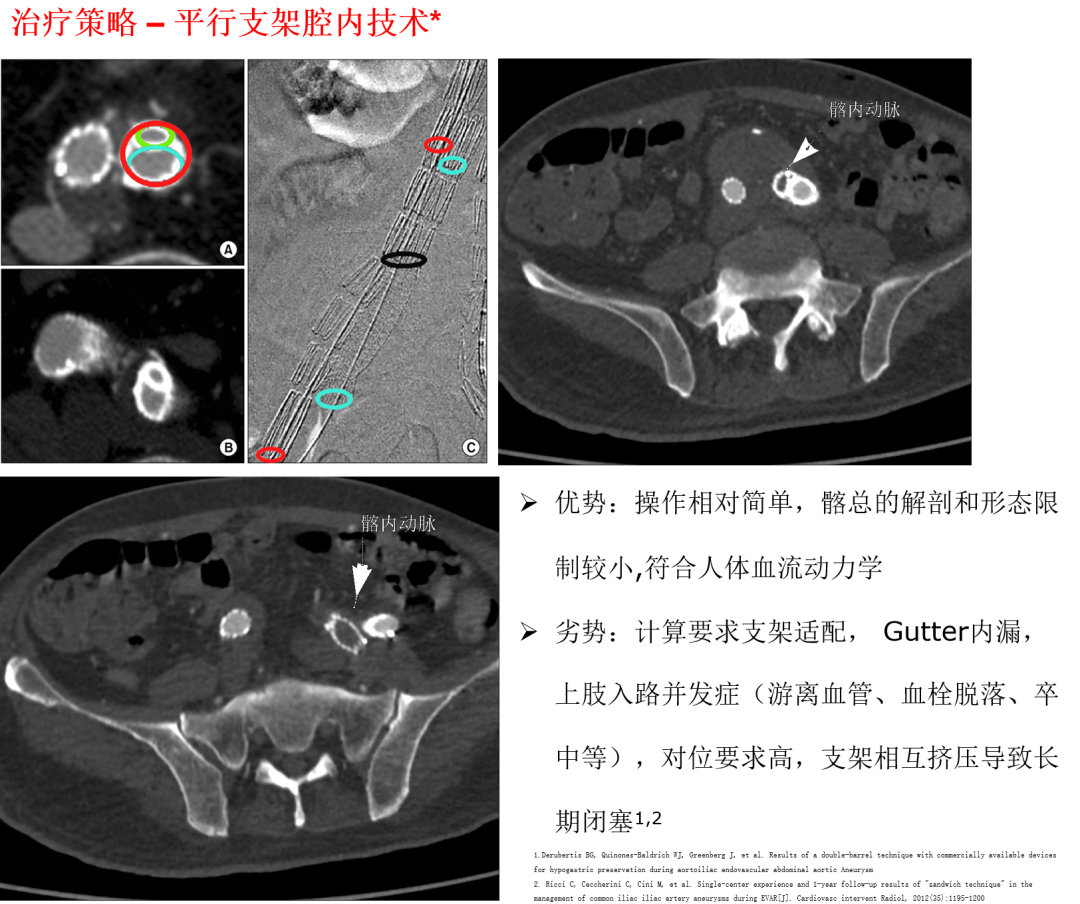

平行支架腔内技术

适应证:髂总动脉直径>15mm ,上肢入路良好(无严重血管扭曲或闭塞)。

操作要点:双支架平行植入髂总动脉 ,技术成功率88%-100% ,但6个月通畅率88%。

优势:操作相对简单 ,符合血流动力学;

风险:存在Gutter内漏、支架挤压闭塞风险 ,且依赖上肢入路 ,可能引发血栓脱落、卒中并发症。